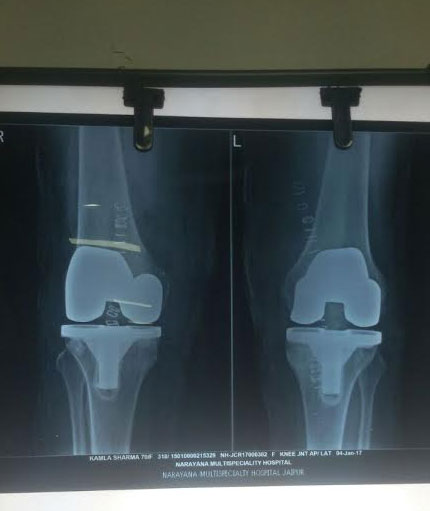

Knee Replacement

Knee replacement surgery otherwise knee arthroplasty, is a surgery involving the replacement of the damaged, diseased or distorted joint surfaces of the knee, with a prosthesis. As per the condition of the patient’s knees, the surgery can be performed as a partial knee replacement surgery or the total knee replacement surgery.